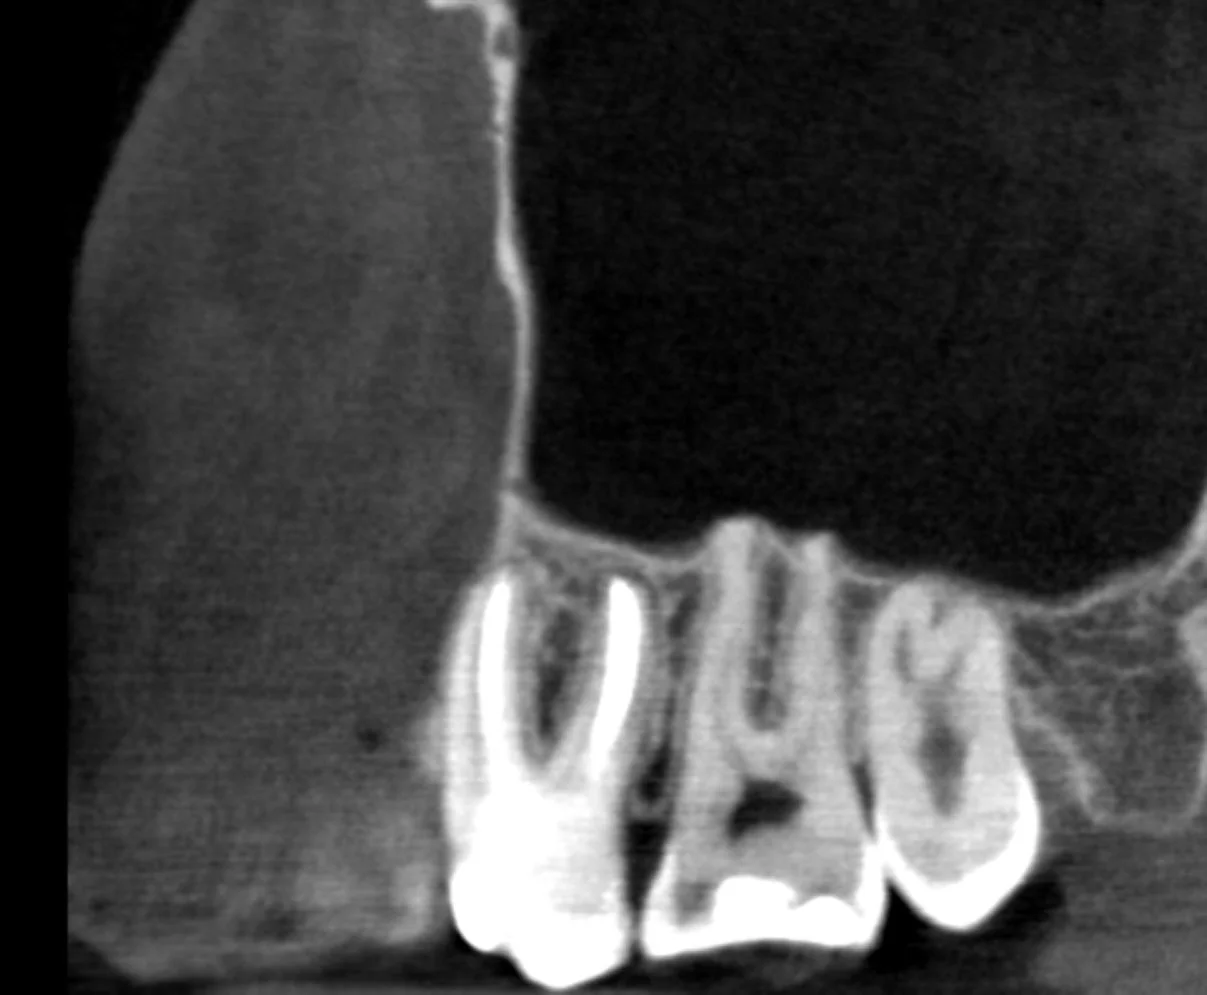

Leczenie kanałowe po dawnym leczeniu amputacyjnym wykonanym ponad 30 lat temu. Masywne obliteracje w przebiegu leczenia.

Pacjent w trakcie gojenia